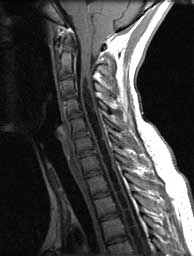

T1 sagittals pre gad

Septated CSF signal cavity expanding the cord from C3 down. Cerebellar tonsils herniated well below the posterior arch of C1.